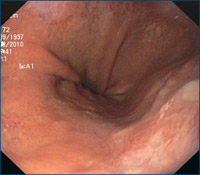

Magenspiegelung mit Kontrastverstärkung im Bereich der unteren Speiseröhre bei Verdacht auf Barrett-Syndrom mit Narrow Band Imaging (NBI). Durch einen speziellen Filter kann die Kontrastierung bei der Betrachtung im Bereich der unteren Speiseröhre so angehoben werden, dass geringe Veränderung der Schleimhaut in der Endoskopie erkannt und durch gezielte Gewebeprobenentnahmen weiter differenziert werden können.